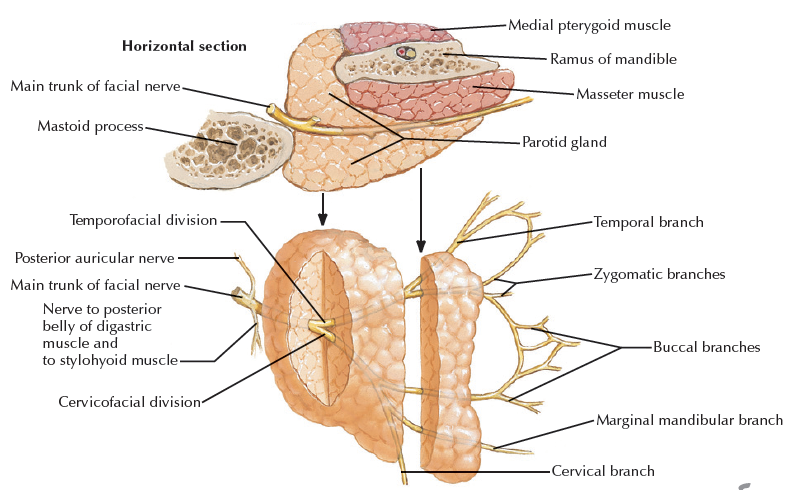

CN VII

Parotid plexus(支配表情肌)

- Temporal br.

- Zygomatic br.

- Buccal br.

- Marginal mandibular br.

- Cervical br.

Parotid plexus